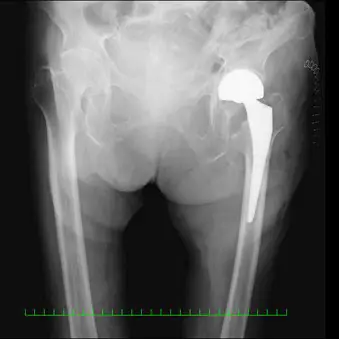

術後単純レントゲン像